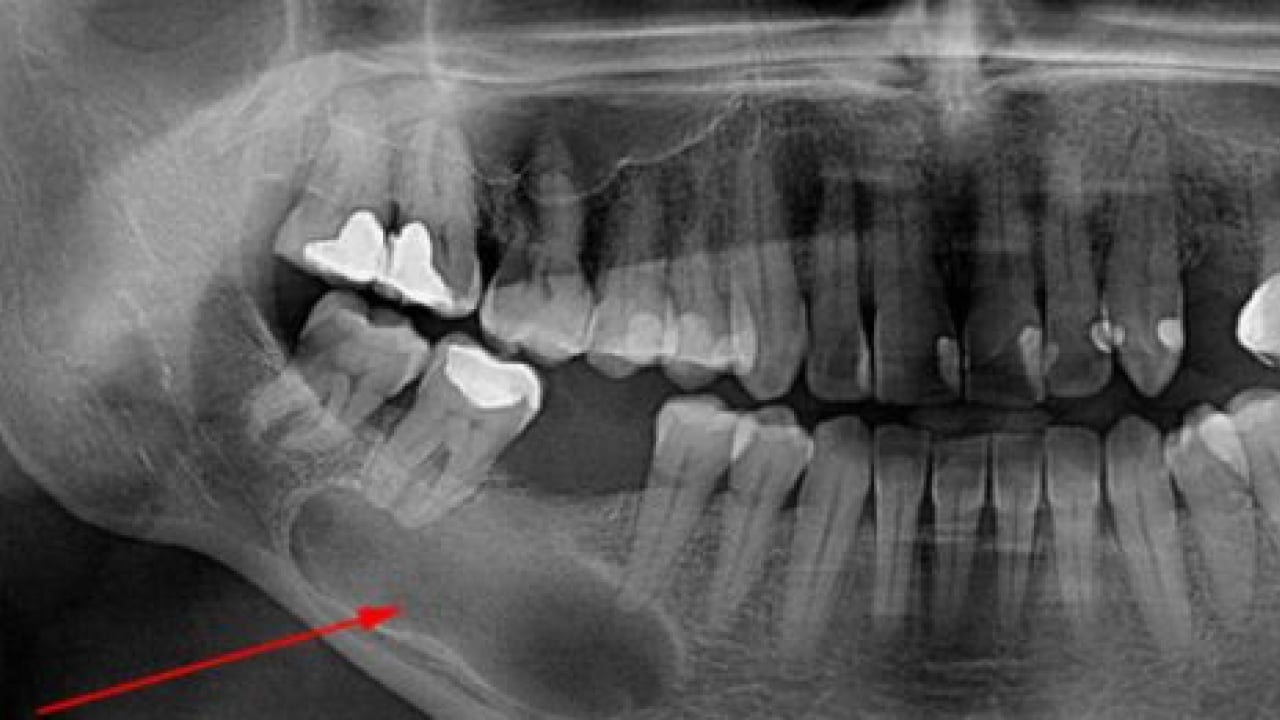

“TEDAVİ YAPILMAZSA DOKU HASARINA YOL AÇABİLİR” Kanal tedavisi yapılmazsa dişte veya vücutta hangi sorunlar görülebileceğine değinen Dr. Öğr. Üyesi Sezer, "Kanal tedavisi yapılmadığında kök ucunda oluşan lezyonlar büyüyerek kistleşebilir, büyük kemik kayıplarına ve doku hasarına yol açabilir. Dişte sürekli hassasiyet ve spontan ağrılar oluşabilir. Kronikleşmiş enfeksiyonlar bazen akut şekilde ani yüz şişliklerine dönüşebilir yahut ağrı vermese bile zaman içinde ilerleyebilir. Ağız içindeki bu enfeksiyon odakları diyabet, kalp hastalıkları gibi sistemik durumları kötü etkileyebilir. Dişlerin tedavi edilmeyip durumları kötüleştiğinde çekilmek zorunda kalınması, çiğneme fonksiyonunda bozulmaları ve bununla beraber bağışıklık sisteminin zayıflamasını da beraberinde getirir" dedi.

“TEDAVİİYİ ERTELMENİN RİSKLERİ” Tedaviyi ertelemenin diş sağlığına etkilerinden bahseden Dr. Öğr. Üyesi Sezer, "Tedavinin ertelenmesi enfeksiyonun ilerlemesine, daha büyük lezyonların oluşmasına, ağrıların artmasına ve dişin çekilme riskine yol açar. Ayrıca enfeksiyonun sistemik hastalıklarla etkileşme ihtimali artar. Erken müdahale hem dişi korur hem de komplikasyon riskini azaltır" açıklamasında bulundu.